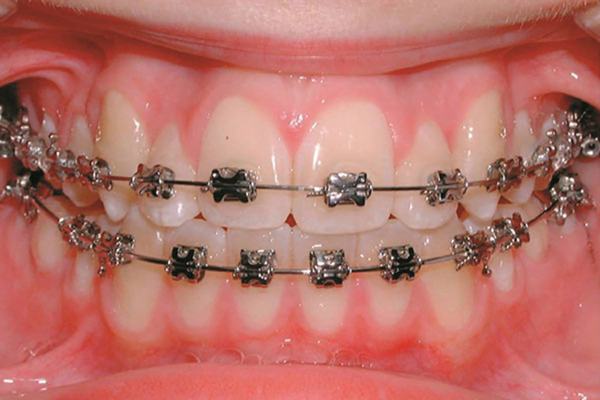

Dental Clinic in Narasimhanaickenpalayam

At GuGu Dental Clinics, we take delight in being one of the most trusted dental clinics in Narasimhanaickenpalayam, supplying whole oral care for the complete own family. From routine checkups to advanced dental treatments, our team of professional dentists ensures that every patient gets personalized and extremely good care.